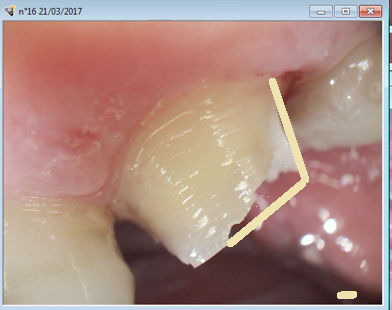

Pourquoi tu n'as pas restoré la dent avant de faire le taille Chico? Si tu avais obturé et taillé apres ca aurait fait comme dans la photo et t'aurais pu couronné direct.

> Pourquoi tu n'as pas restoré la dent avant de faire le taille Chico? Si tu

> avais obturé et taillé apres ca aurait fait comme dans la photo et t'aurais pu

> couronné direct.

Parce que ca n'est pas l'indication d'un SC33 mais d'un inlay core. Mais t'inquiètes je couronne direct pareil. -)

Après préparation j'ai estimé que l'inlay core était plus indiqué. Mais tu peux penser l'inverse.